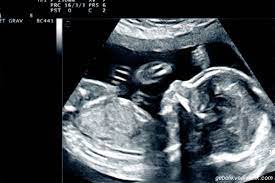

Hamilelik döneminde bebeğin cinsiyetini belirlemek için ultrason muayenesi yapılır.

Anne karnındaki bebek gelişiminin aylara göre tamamlanmasıyla, bebeklerin cinsiyeti öğreniliyor. Bebeğin cinsiyetini öğrenmek kolay aslında. Hamilelik döneminde bebeğin cinsiyetini belirlemek için ultrason muayenesi yapılır. Bebek cinsiyeti tahmin edilebilir mi? Bebeğin cinsiyeti önceden belirlenebilir mi? Erkek bebek nasıl belli olur? Haftasına kadar belli olur yanıtıdır.20. Bebek cinsiyeti ne zaman belli olur? Ancak kız denilen bebeklerde yanılma daha sıktır çünkü penisin görülememesi kız olduğu yanılgısını yaratabilir. Bebeğin cinsiyetini önceden tahmin etmenin ipuçları konumuzda yer alıyor.